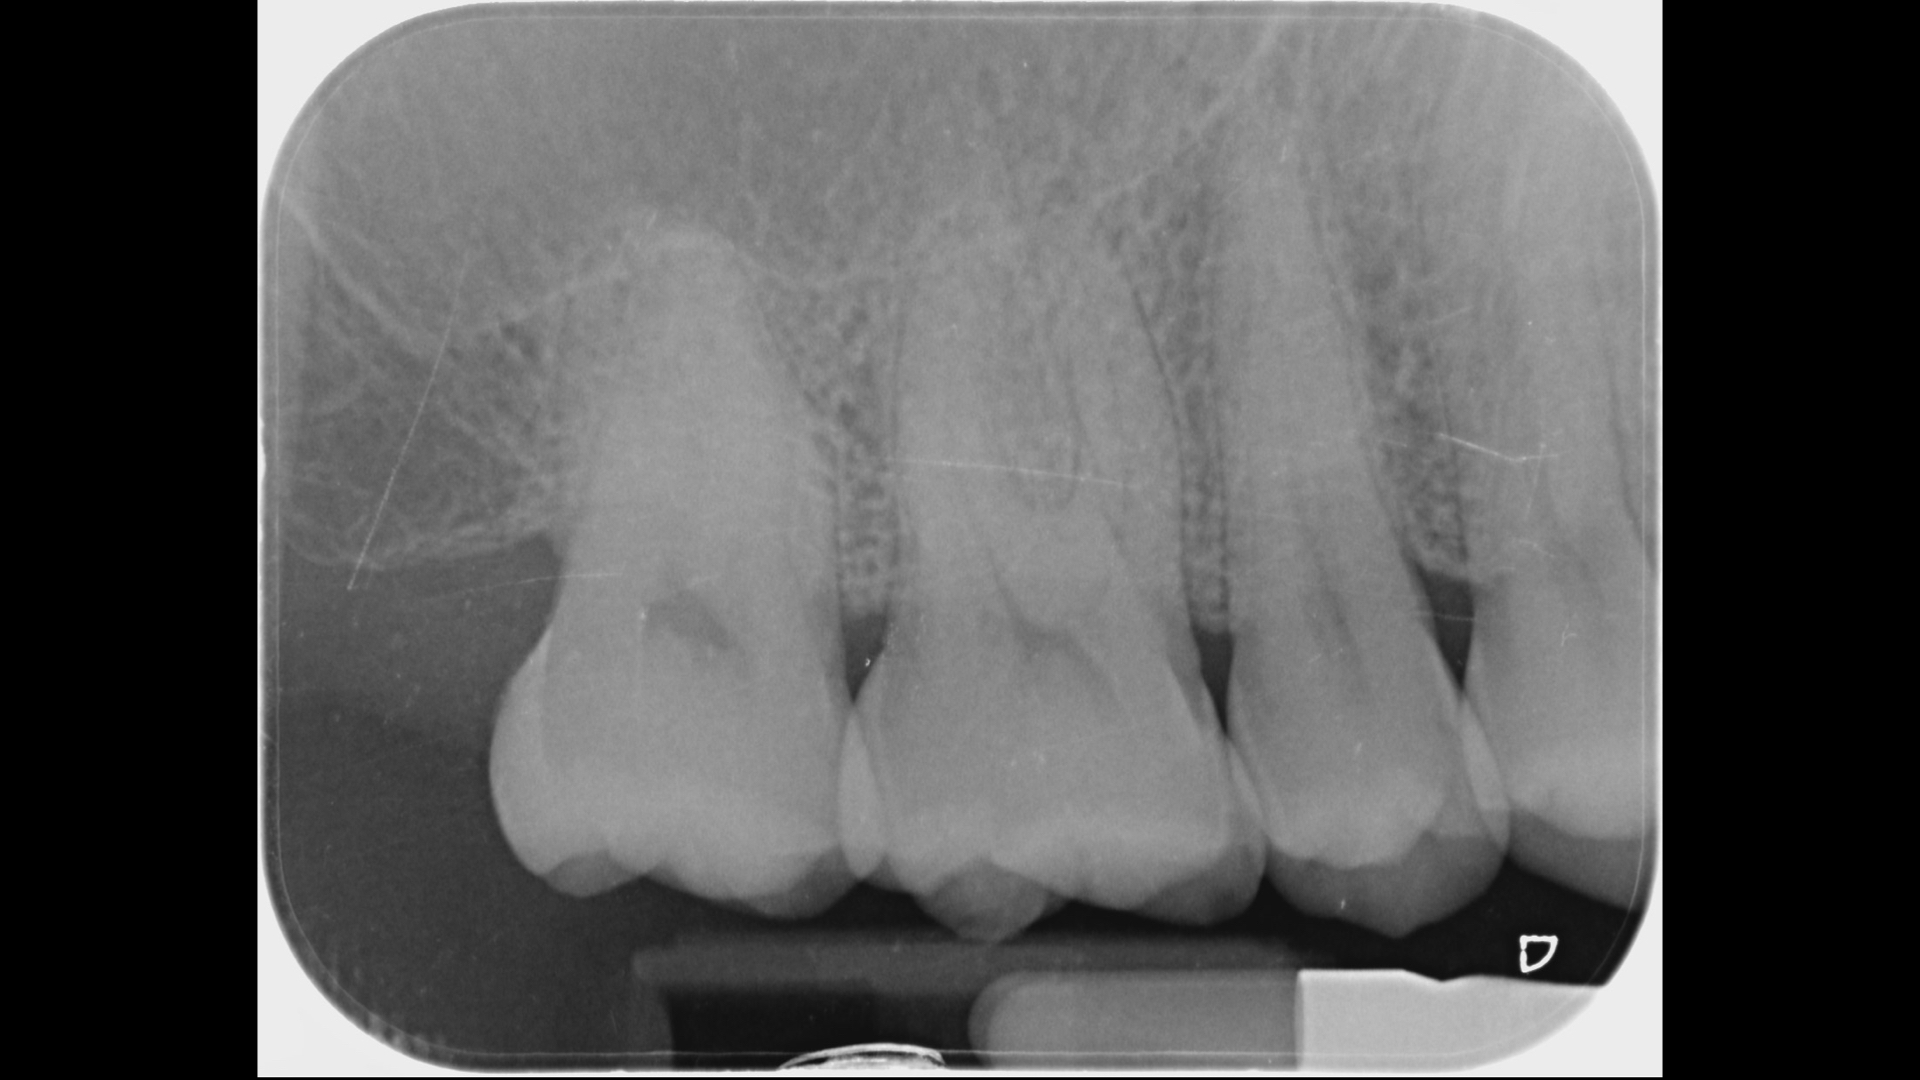

裂痕登發現牙齒有裂痕

初期X光檢查沒有發現異狀